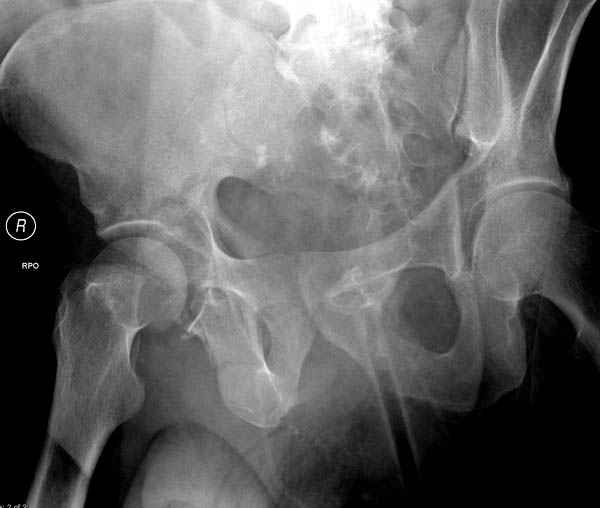

Дополнительно имеется перелом ацетабулума: задняя

колонна с полупоперечным переломом, и переломы костей лица.

На седьмой день зафиксирован перелом ацетабулума через задний доступ. Перед операцией для профилактики DVT, IVC фильтер, также получает Lovenox.

По снимку создается впечатление о высоком поперечном переломе, задней колонны, стенки; почему не пользовались *magic screw*?

По возможности вышлите снимки, сканы таза до

реконструкции, интраоперационные.

Там множество обычных 2.7 мм шурупов, потом идет фиксация основными пластинами.